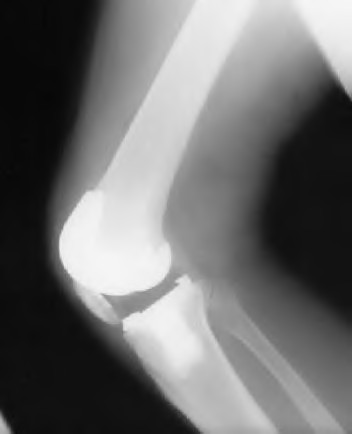

The radiograph seen in Figure A reveals varus alignment of the knee, with medial tibial deficiency; from this X-ray the patient appears to have unicompartmental arthritis. Treatment options for unicompartmental arthritis include high tibial osteotomy, interpositional arthroplasty, unicondylar knee replacement and total knee replacement. Interpositional arthroplasty became popular in the 1950’s when early outcomes analysis seemed to indicate good results; long term follow up in one study found 0/12 excellent results, with all patients requiring conversion to TKA. This procedure is no longer recommended due to the poor long term outcomes.

While an osteotomy is still used for young and active patients, unicompartmental or total knee arthroplasty have largely replaced this treatment in older patients. Advantages of UKA and TKA include more predictable relief of pain, quicker recovery, and better long-term results. Criteria for UKA include limited unicompartmental disease, no more than a fixed 10 degrees of varus or 5 degrees of valgus deformity from neutral and an intact anterior cruciate ligament with no signs of medial lateral subluxation of the femur on the tibia; this patient is therefore not a good candidate for this procedure.

Total knee arthroplasty can be used to provide predictable pain relief in a patient with unicompartmental and tricompartmental degenerative disease and varus malformation of the knee and for this patient is the best option.